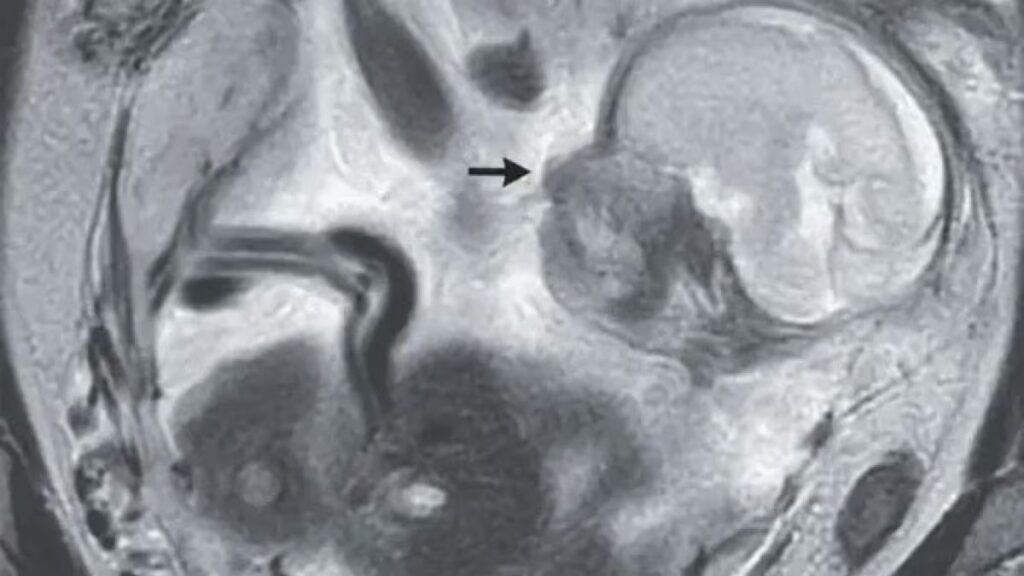

I risultati ottenuti sono straordinari: una bambina affetta da atrofia muscolare spinale (Sma) è stata trattata con una terapia innovativa mentre era ancora nella pancia della madre. Oggi, a distanza di due anni e mezzo dalla nascita, la piccola non presenta alcun sintomo.

Tale ricerca è stata effettuata grazie ad un farmaco, il risdiplam, somministrato alla madre quando era incinta e in grado di agire sulla componente genetica della malattia.

Alla nascita della bambina gli esami hanno confermato la precedente diagnosi di Sma, ma hanno anche sottolineato come il farmaco somministrato in gravidanza avesse raggiunto il feto.

La bambina, infatti, non presentava alcun sintomo già al momento della nascita.

Dopo la prima settimana di vita, la cura con risdiplam è stata ripresa, con l’obiettivo di garantire una totale copertura per la bambina. La sua salute è ora in perfette condizioni, ma probabilmente il farmaco dovrà essere assunto per tutta la vita.